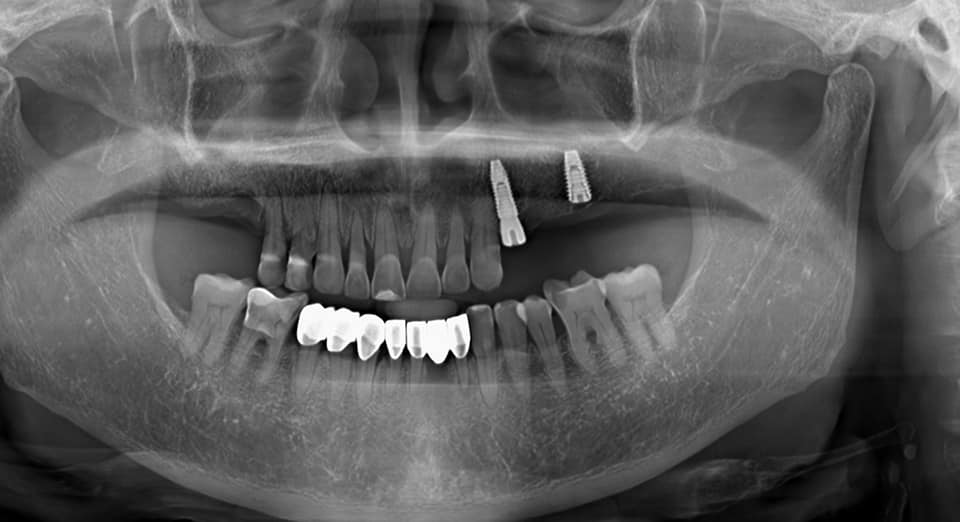

Tiếp tục là những ca cấy ghép implant nhẹ nhàng, không đau, hạn chế xâm lấn tại nha khoa Thiện An BMT – Đăk Lăk do BS. CK2 Huỳnh Thanh Trung trực tiếp thực hiện

Cấy ghép implant là kỹ thuật trồng răng giả bằng cách cấy vào xương hàm tại vị trí chân răng cũ một chiếc chân răng nhân tạo, sau đó trồng lên chân răng một chiếc răng khác thay thế răng đã mất phục vụ cho mục đích thẩm mỹ hoặc ăn nhai

Continued to be gentle, painless, minimally invasive implant cases at Thien An BMT Dental Clinic – Dak Lak by Dr. CK2 Huynh Thanh Trung directly performed

Implant is a technique of planting false teeth by implanting an artificial tooth root into the jawbone at the old tooth root position, then planting another tooth on the root to replace the lost tooth for aesthetic purposes. or chew